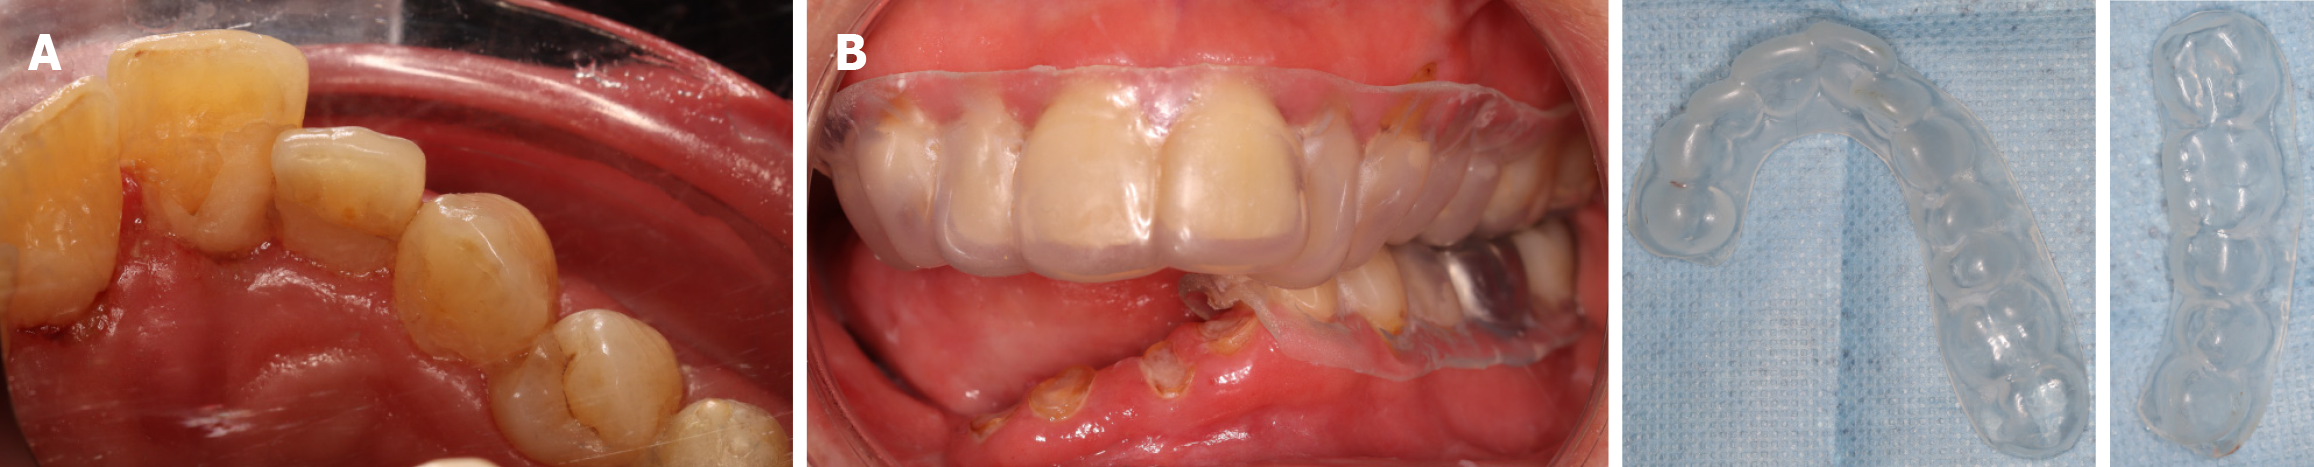

The treatment plan aimed to restore oral function and aesthetics in a patient who had undergone extensive surgical reconstruction after cancer therapy. This multidisciplinary approach addressed dental decay, occlusal dysfunction, radiation-induced complications, and facial asymmetry secondary to soft tissue and bone loss. The patient’s dental care focused on restoring function and aesthetics while treating complications resulting from oncology treatment. Initial management focused on the conservative treatment of carious lesions using minimally invasive techniques. Selective excavation was performed via a palatal approach, followed by the placement of glass ionomer restorations or biodentine, as indicated. Root remnants were preserved to reduce the risk of osteoradionecrosis, a critical consideration in irradiated tissues. Additionally, temporary direct composite restorations were placed on teeth 26 and 27 to facilitate progressive mouth-opening exercises (Figure 3A).

Oral hygiene protocols were reinforced through patient education, including individualized instruction on brushing technique and the recommendation of agents to stimulate salivary flow[13,25]. A custom fluoride tray was fabricated from digital impressions to aid in the prevention of radiation-induced dental caries. A 2000 ppm fluoride gel was prescribed for lifelong use, with the patient demonstrating high compliance, requiring only minor modifications to accommodate gingival sensitivity[26,27]. Fluoride trays are presented in Figure 3B.

An optical impression was captured using the 3Shape intraoral scanner[28], and a transitional mandibular removable prosthesis with a hard base was fabricated, extending from teeth 32 to 46. This prosthesis served multiple functions: Re-establishing posterior occlusal support, enhancing masticatory efficiency, stabilizing the occlusal relationship, and contributing to neuromuscular and temporomandibular joint rehabilitation. Due to the presence of residual roots and the associated risk of osteoradionecrosis, extractions were deferred when clinically feasible[29]. The prosthesis also provided external labial support and partially compensated for jugal soft tissue loss, contributing to improved facial contour (Figure 4). To address residual facial asymmetry and volume loss, HA injections were administered, with particular attention to the right perioral and lower facial regions. The HA injections improved tissue hydration, restored structural support, and helped correct scar-associated contour deformities. This intervention significantly enhanced the patient’s facial aesthetics and psychosocial well-being, providing an important adjunct to the overall reconstructive strategy[12,14].